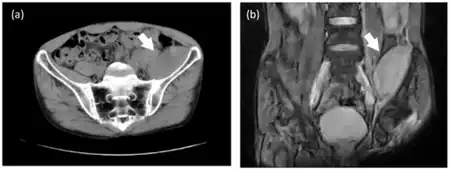

Pelvic computed tomography of individual with factor XIII deficiency a) transverse plane and b) coronal plane.